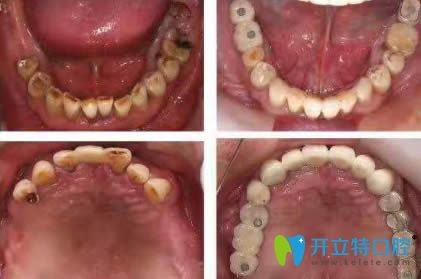

劉奎恒愿速生牙效果圖賞析: